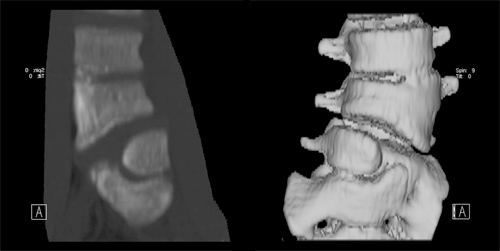

Three-dimension CT scan of the spine showing a hemi vertebra

3차완 CT 영상 검사 상 반척추 형태